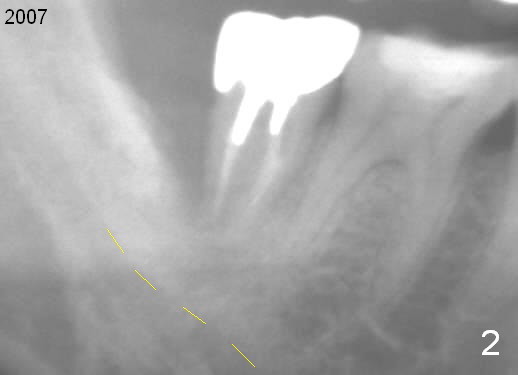

A 44-year-old man has had an asymptomatic distal defect of the tooth #31 for 8 years (Fig.1-5). Recently there is an acute episode of swelling and pain. A fistula develops mesiobucally. Panoramic X-ray films tend to show that the distal defect is deep (Fig.2,5; yellow dashed line: upper border of the Inferior Alveolar Canal). In addition, the distal defect may be not even buccolingually, as indicated by white and red arrowheads in Fig.3,4. Following placement of a 6.9x10 mm bone-level implant, a 7.8x4 (4.5) mm cemented abutment is inserted for try in (Fig.6). When it is fit, it is removed and a cover screw is temporarily placed. A piece of Osteotape (~10x4 mm) is placed distobuccally or distolingually (depending upon which wall is lower). A small amount of bone graft is packed between the most coronal portion of the implant and the Osteotape. The cover screw is then removed and the abutment is re-inserted and tightened by hand. An immediate provisional is fabricated with well-trimmed margin. Reline is done if necessary for securely holding bone graft in place. A new PA is to be taken prior to surgery to determine the extent of the lesion. Photos are taken to show the mesiobuccal fistula. Return to Lower Molar Immediate Implant Xin Wei, DDS, PhD, MS 1st edition 04/12/2015, last revision 05/25/2018